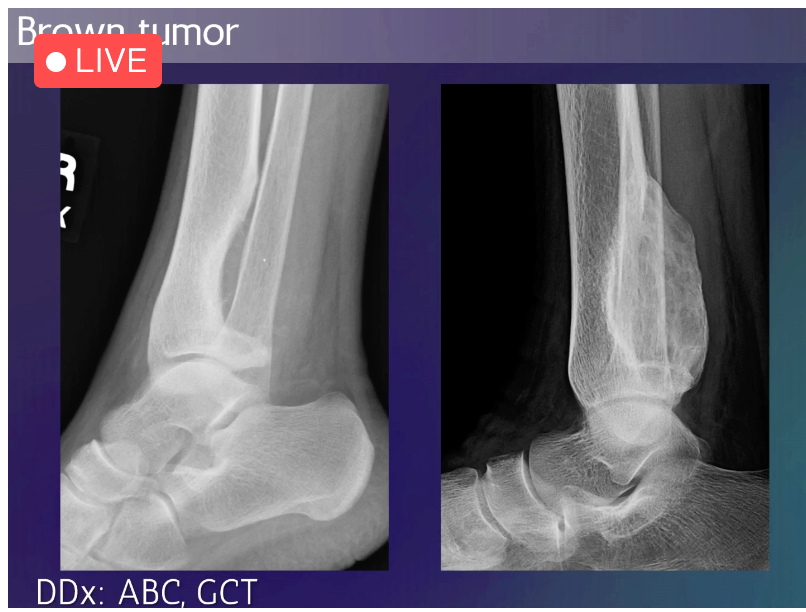

ABC